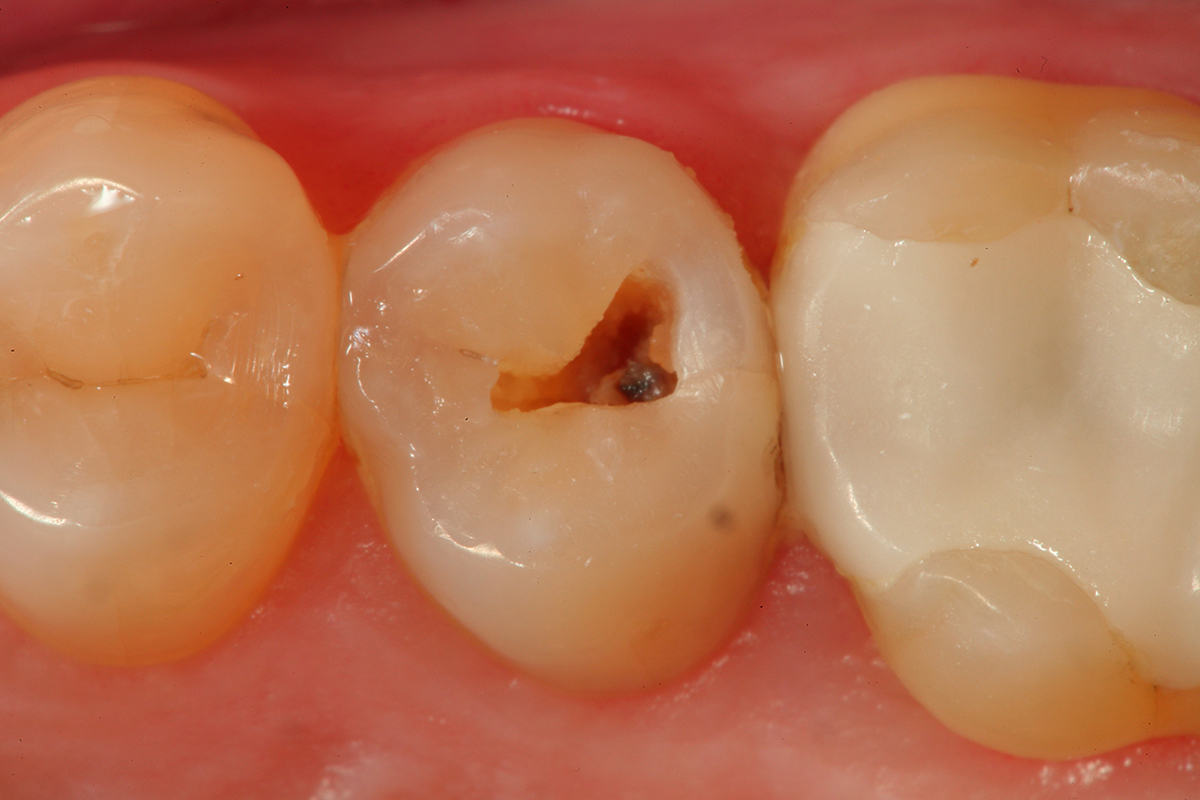

Fig 2. After a fissurotomy bur is used to conservatively open into the groove, a rather extensive carious area is discovered.

Figure 2